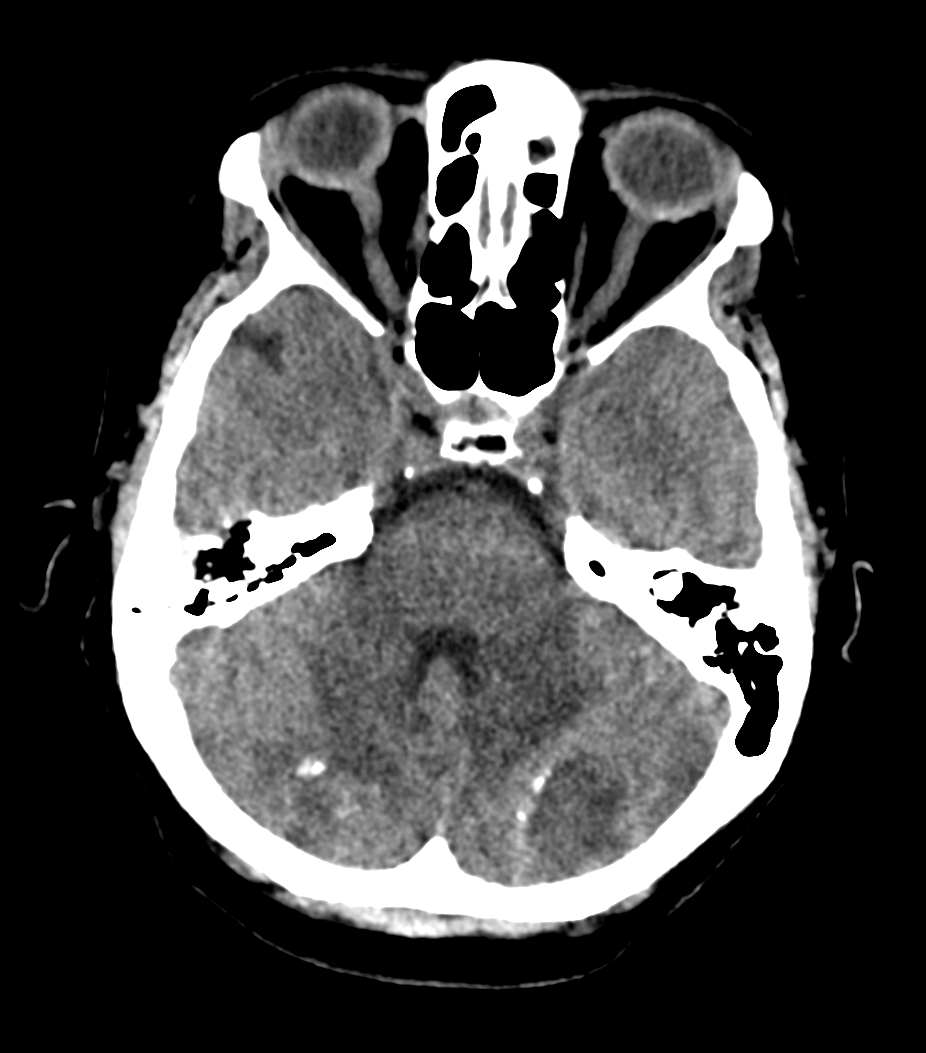

Caso 44

Licia Andreana Fenu